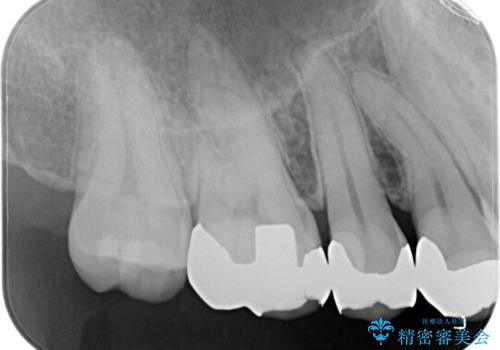

- 銀歯のセラミックへのやり替えをご希望で来院されました。

銀歯が入ってる歯は複数箇所ありましたが、咬合力がより強く破折リスクが高い奥歯から治療を開始してます。

奥歯の噛み合わせが強く、治療後にセラミックが割れるリスクがあった為マウスピースの装着をして頂いてます。

他の銀歯については患者様のご希望のタイミングで治療していく予定です。